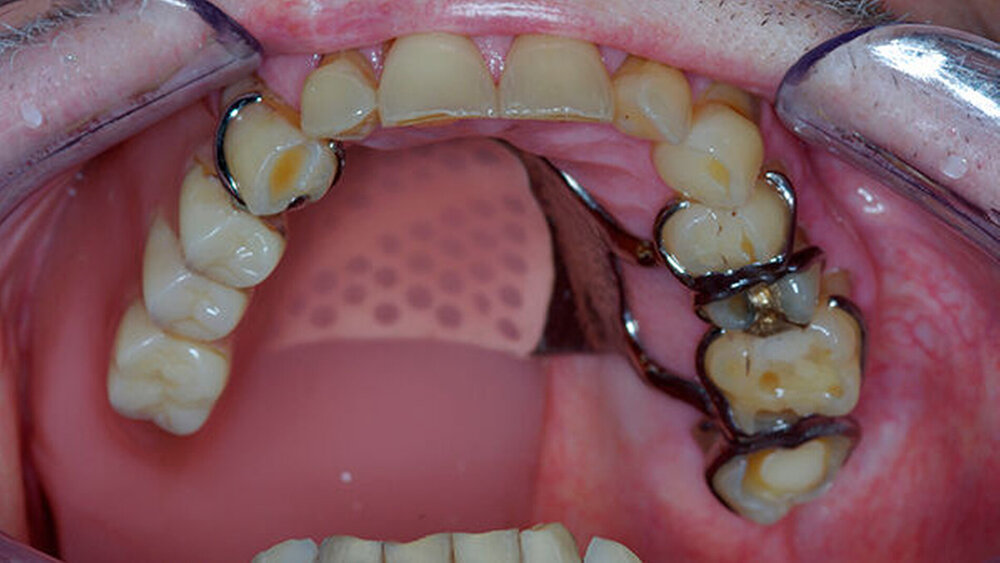

Das Verzeichnis bezieht sich in erster Linie auf Behandlungsorte, an denen intraorale defektprothetische Versorgungen durchgeführt werden. Falls auch extraorale Behandlungen durchgeführt werden, ist dies extra vermerkt. Für die Suche nach rein epithtetischen Behandlungsorten wird auf die Website desDeutschen Bundesverbandes der Epithetiker e.V.verwiesen.